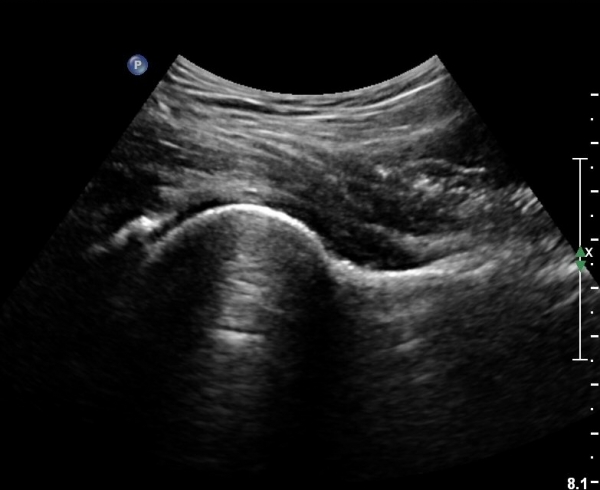

[¾ûµ¢ÀÌ] ¾ûµ¢ÀÌ °üÀý¼ø ÆÄ¿­ÀÇ ÃÊÀ½ÆÄ°Ë»ç(ultrasonography of labrum tear of hip joint)

Sonography of the Acetabular Labrum Visualization of Labral Injuries During Intra-Articular Injections

What is the role of clinical tests and ultrasound in acetabular labral tear diagnostics?

Sonographic evaluation of anterosuperior hip labral tears with magnetic resonance arthrographic and surgical correlation.